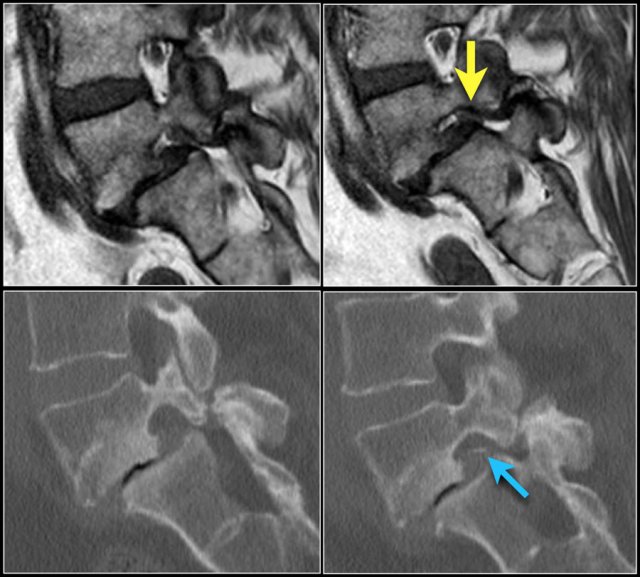

Here a disc herniation with upward migration.

By using the marker, you can correlate the abnormality on the T1W-image with the axial T2W-images.

On the T2W-image it is more obvious that this is a disc herniation.

The lower images are with the marker on.

you may have to enlarge the images to see it.

These foraminal disc herniations can be easily overlooked.

Notice how subtle the findings are on the axial T2W-images.

The herniated disc can be easily mistaken for the nerve root.

The sagittal T1W-image shows the upward migration of the disc.